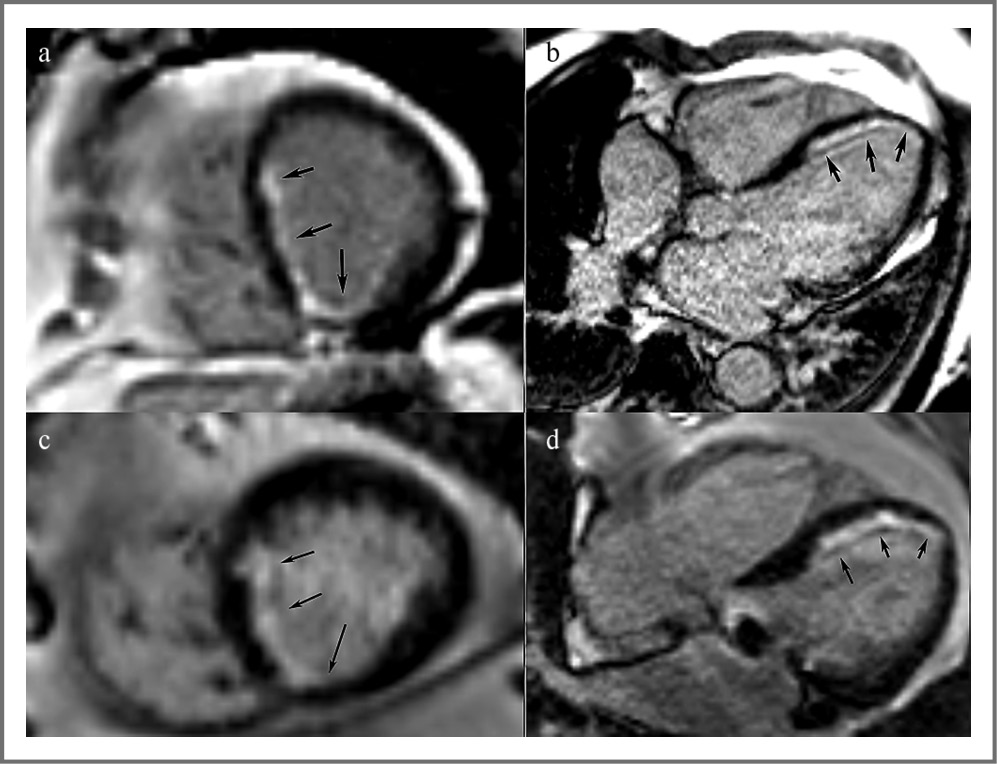

Рис. 1. МРТ сердца, кино-МРТ (импульсная последовательность True FISP). Четырехкамерное сечение. Диастола (a, b), систола (c, d). Изображения до лечения (a, c) и после лечения (b, d).

Исследование МРТ показало, уменьшение размеров полости ЛЖ как в диастолу (КДР ЛЖ уменьшился с 7,3 до 6,3 см), так и в систолу (КСР снизился с 6,1 до 4,5 см), в результате снижение ФВ ЛЖ отмечалось с 34 до 43%. При этом полость ЛП достоверно не изменилась.

Fig. 1. Cardiac MRI, Cine MRI (pulse sequence True FISP). Four-chamber section. Diastole (a, b), systole (c, d). Images before treatment (a, c) and after treatment (b, d).